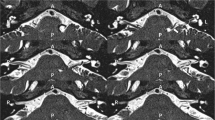

Two types of LSR can be recorded by stimulating the upper and the lower branches of the facial nerve on the symptomatic side of HFS. By stimulating the zygomatic branches of the facial nerve on the symptomatic side, LSR can be recorded from the mentalis muscle. In addition, LSR can be also obtained from the orbicularis oculi muscle or the frontalis muscle by stimulating mandibular branch (Fig. 2). Constant current stimuli are applied for 0.1–0.2 ms with a bar electrode. Resting motor threshold (rMT) is initially defined as the minimum intensity that could induce the amplitude of LSR of >10 μV in at least five successive trials. After defining the rMT, the LSR can be obtained by stimulating rectangular shock with a suprathreshold strength.

The results of Møller and Jannetta’s study about the origin of lateral spread response (LSR). (a) Schematic diagram of LSR method used in this study. The LSR was recorded from orbicularis oculi muscle by stimulating mandibular branch of facial nerve. (b) The difference between the actual measured value ant the calculated value of the latency of the LSR. The latency of the LSR from the orbicularis oculi muscle by stimulating the mandibular branch was larger than the sum of the conduction time from the points of stimulation of the mandibular branch to the root exit zone (REZ) of facial nerve and from REZ of the facial nerve to the orbicularis oculi muscle